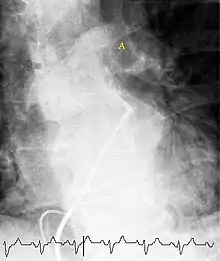

(A) After inhalation of 20 mCi of Xenon-133 gas, scintigraphic images were obtained in the posterior projection, showing uniform ventilation to lungs.

(B) After intravenous injection of 4 mCi of Technetium-99m-labeled albumin, scintigraphic images shown here in the posterior projection. This and other views showed decreased activity in multiple regions.

A ventilation/perfusion scan (or V/Q scan or lung scintigraphy) shows that some areas of the lung are being ventilated but not perfused with blood (due to obstruction by a clot).[17] This type of examination is as accurate as multislice CT, but is less used, due to the greater availability of CT technology. It is particularly useful in people who have an allergy to iodinated contrast, impaired kidney function, or are pregnant (due to its lower radiation exposure as compared to CT).[62][63][64] The test can be performed with planar two-dimensional imaging, or single photon emission computed tomography (SPECT) which enables three-dimensional imaging.[55] Hybrid devices combining SPECT and CT (SPECT/CT) further enable anatomic characterization of any abnormality.[65]